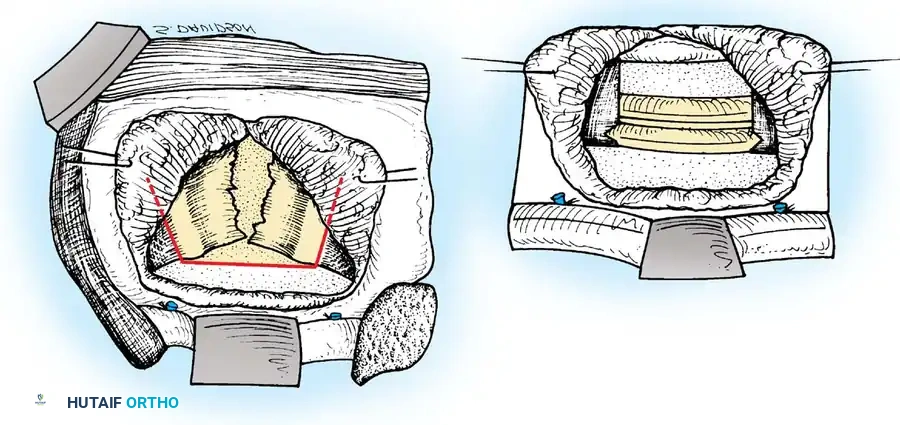

- Palpate the extent of the abscess across the anterior vertebral bodies. Make a T-shaped incision through the thick abscess wall: the transverse limb should be opposite the center of the disease, and the longitudinal limb medial to the ligated intercostal vessels.

- Raise the two triangular flaps to reveal the caseous necrotic core and the destroyed vertebral bodies.

Radical Débridement (Corpectomy)

- Evacuate all liquid pus, caseous debris, and sequestrated bone or disc material using high-powered suction and pituitary rongeurs. If the abscess spans bilaterally, pass the suction tip anterior to the vertebrae into the contralateral cavity to ensure complete evacuation.

- Using osteotomes, high-speed burrs, and rongeurs, radically excise all diseased, sclerotic, and necrotic bone.

- The excision must extend posteriorly to the posterior longitudinal ligament (PLL). Remove the PLL and any tuberculous granulation tissue to fully decompress the ventral dura.

- Crucial Step: Excise the entire affected vertebral body. Tuberculous collections and sequestrated disc fragments frequently hide in the spinal canal posterior to seemingly intact posterior vertebral body walls.

- Remove the intervertebral discs at the cranial and caudal extents of the cavity until normal, bleeding endplates are exposed.